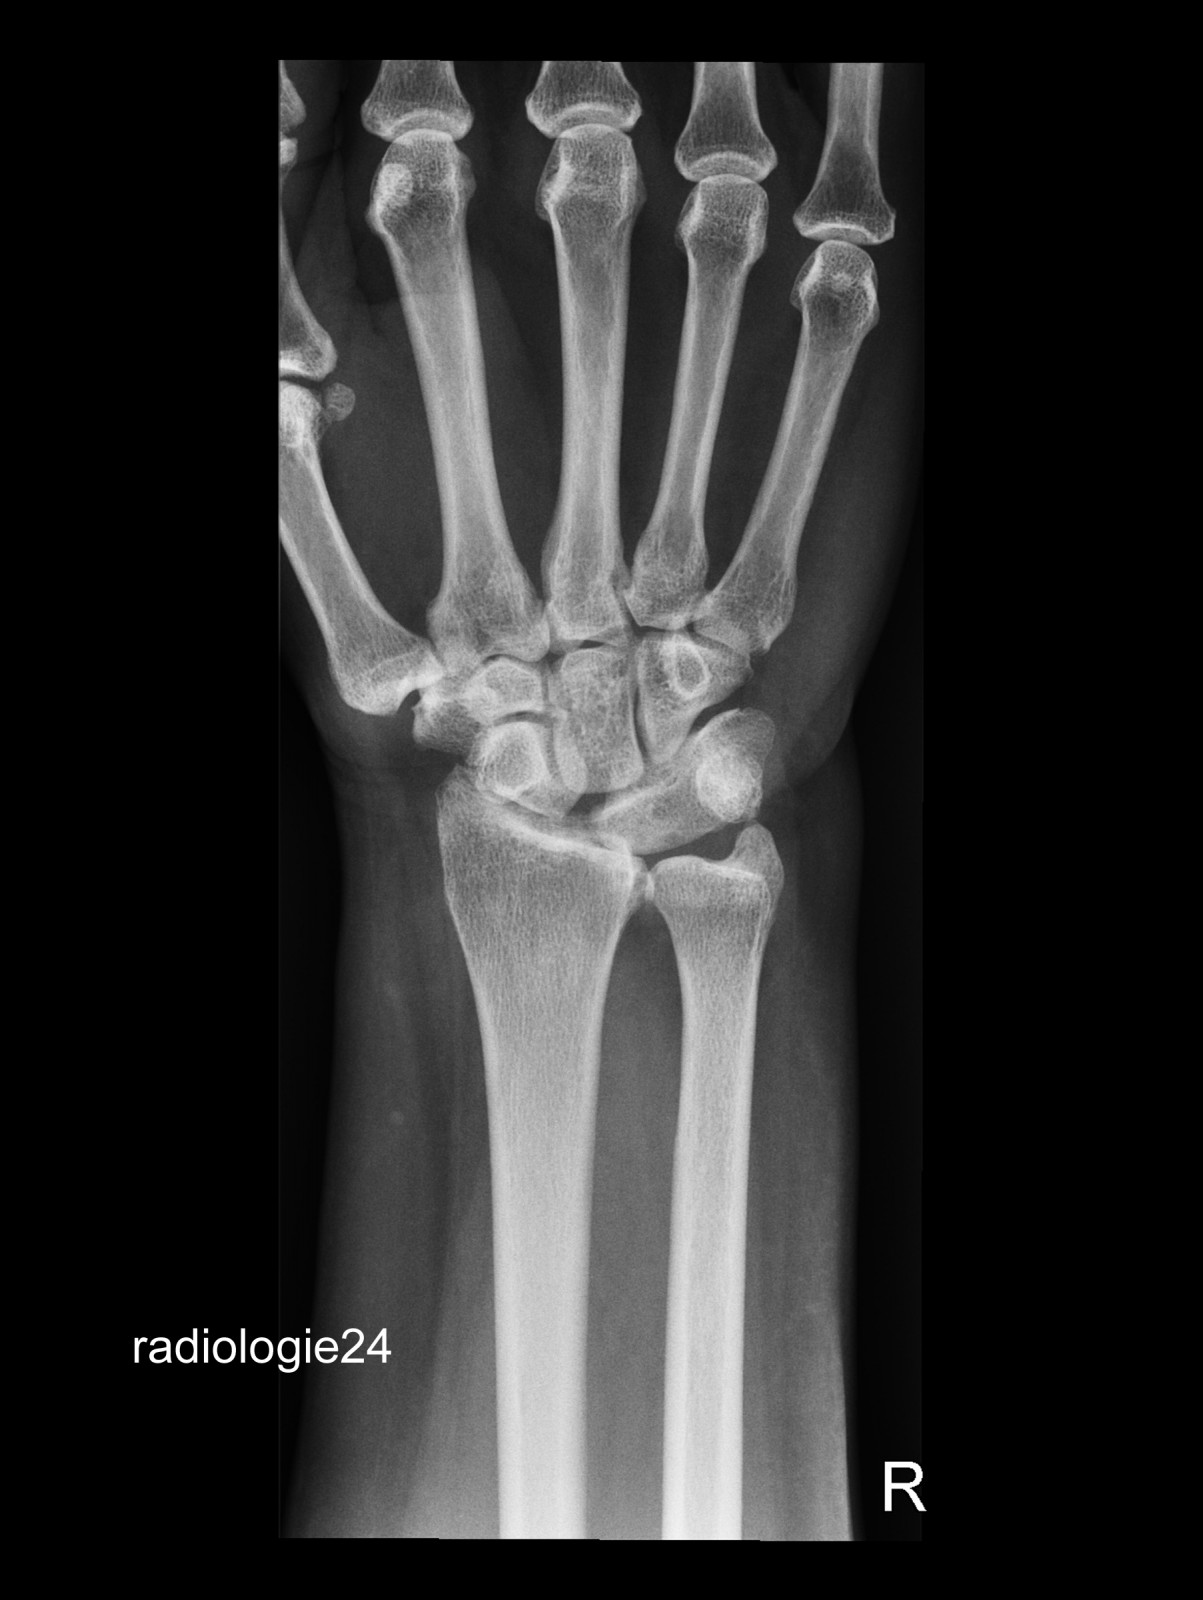

Röntgenfall des Monats Mai 2018 mit Auflösung

71 jähriger Patient Sturz auf die ausgestreckte Hand. Schmerzen. Ihre Diagnose? Weitere Abklärung?

Bild vergrössern

Link zur Auflösung mit ausführlichem Befund:

https://www.radiologie24.ch/radiologie-mediathek/roentgenfall_des_monats